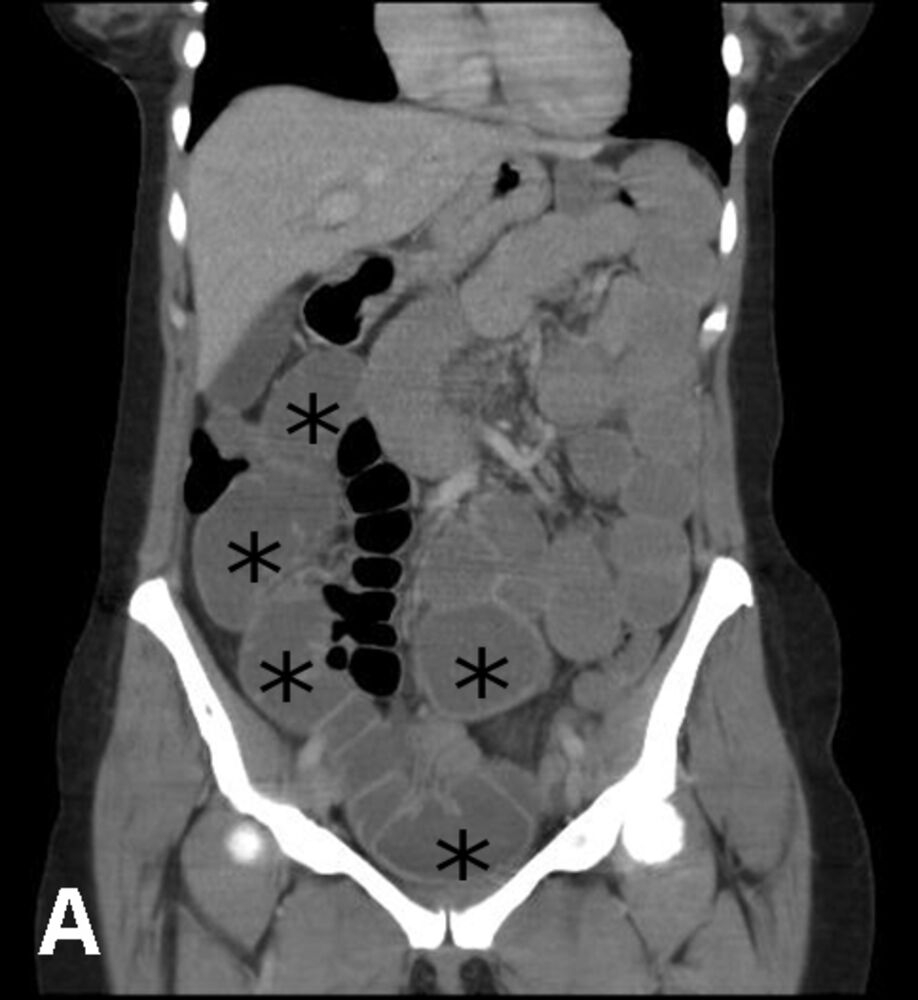

- CT scan of the abdomen and pelvis would show dilated loops of small bowel and any masses present

- CT scan of the abdomen and pelvis with contrast (imaging of choice for diagnosis of LBO) to distinguish between a partial or complete obstruction